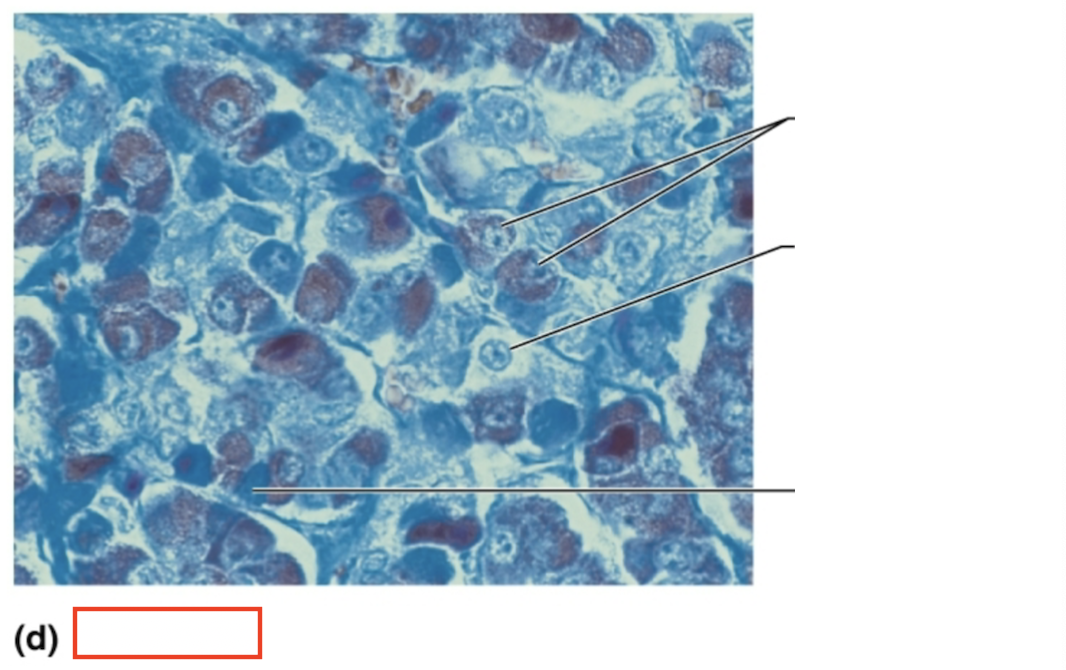

What structure is highlighted?

alpha cells (glucagon producing)

What structure is highlighted?

beta cells (insulin producing)

What structure is highlighted?

pancreatic acinar cells (exocrine)

What tissue is shown?

pancreatic islet

What hormones are released by the pancreas?

insulin, glucagon

What are the target organs and effects of insulin

most cells of the body, accelerates the transport of glucose into body cells; promotes glycogen, fat, and protein synthesis

What are the target organs and effects of glucagon?

primarily the liver and adipose; accelerates the breakdown of glycogen to glucose, stimulates the conversion of lactic acid into glucose, releases glucose into the blood from the liver

What stimulates glucagon production?

decreased blood glucose levels, sympathetic nervous system stimulation

What stimulates insulin production?

increased blood glucose levels, parasympathetic nervous system stimulation